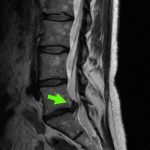

L5S1腰椎間盤突出, 引起神經壓迫和右側嚴重的坐骨神經疼痛,已捱了幾個月!

脊椎微創顯微鏡的神經外科手術

只需要1.5小時和一個2厘米的小傷口,去根治嚴重的神經疼痛

切除突出的椎間盤,為神經根減壓,及移除L5S1椎間盤空間內的退化和鬆散的椎間盤碎片,以防止將來的疾病復發!